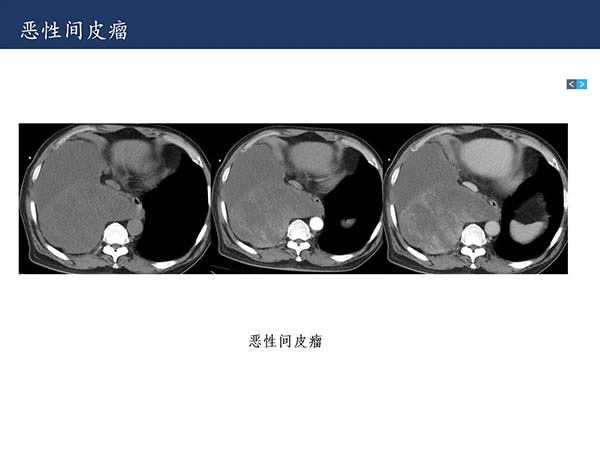

【杨柳科普】肺上皮样血管内皮瘤的影像表现